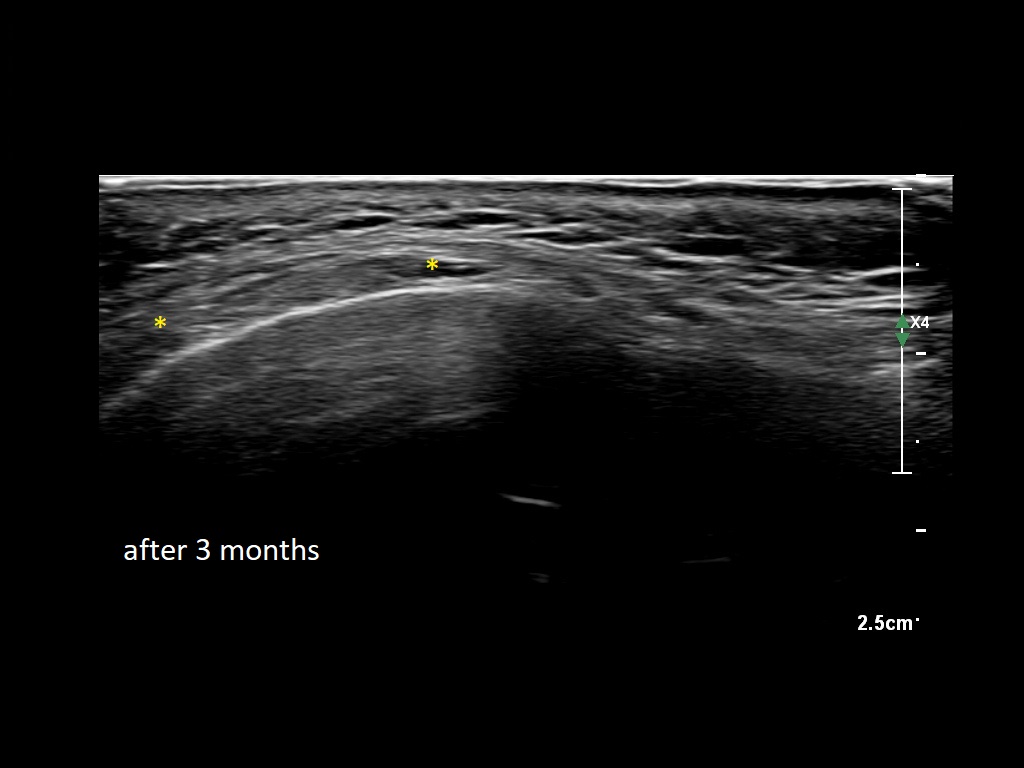

Draw in the second image below where the fillers are located. To check if your answer is correct, swipe the first image to the right.